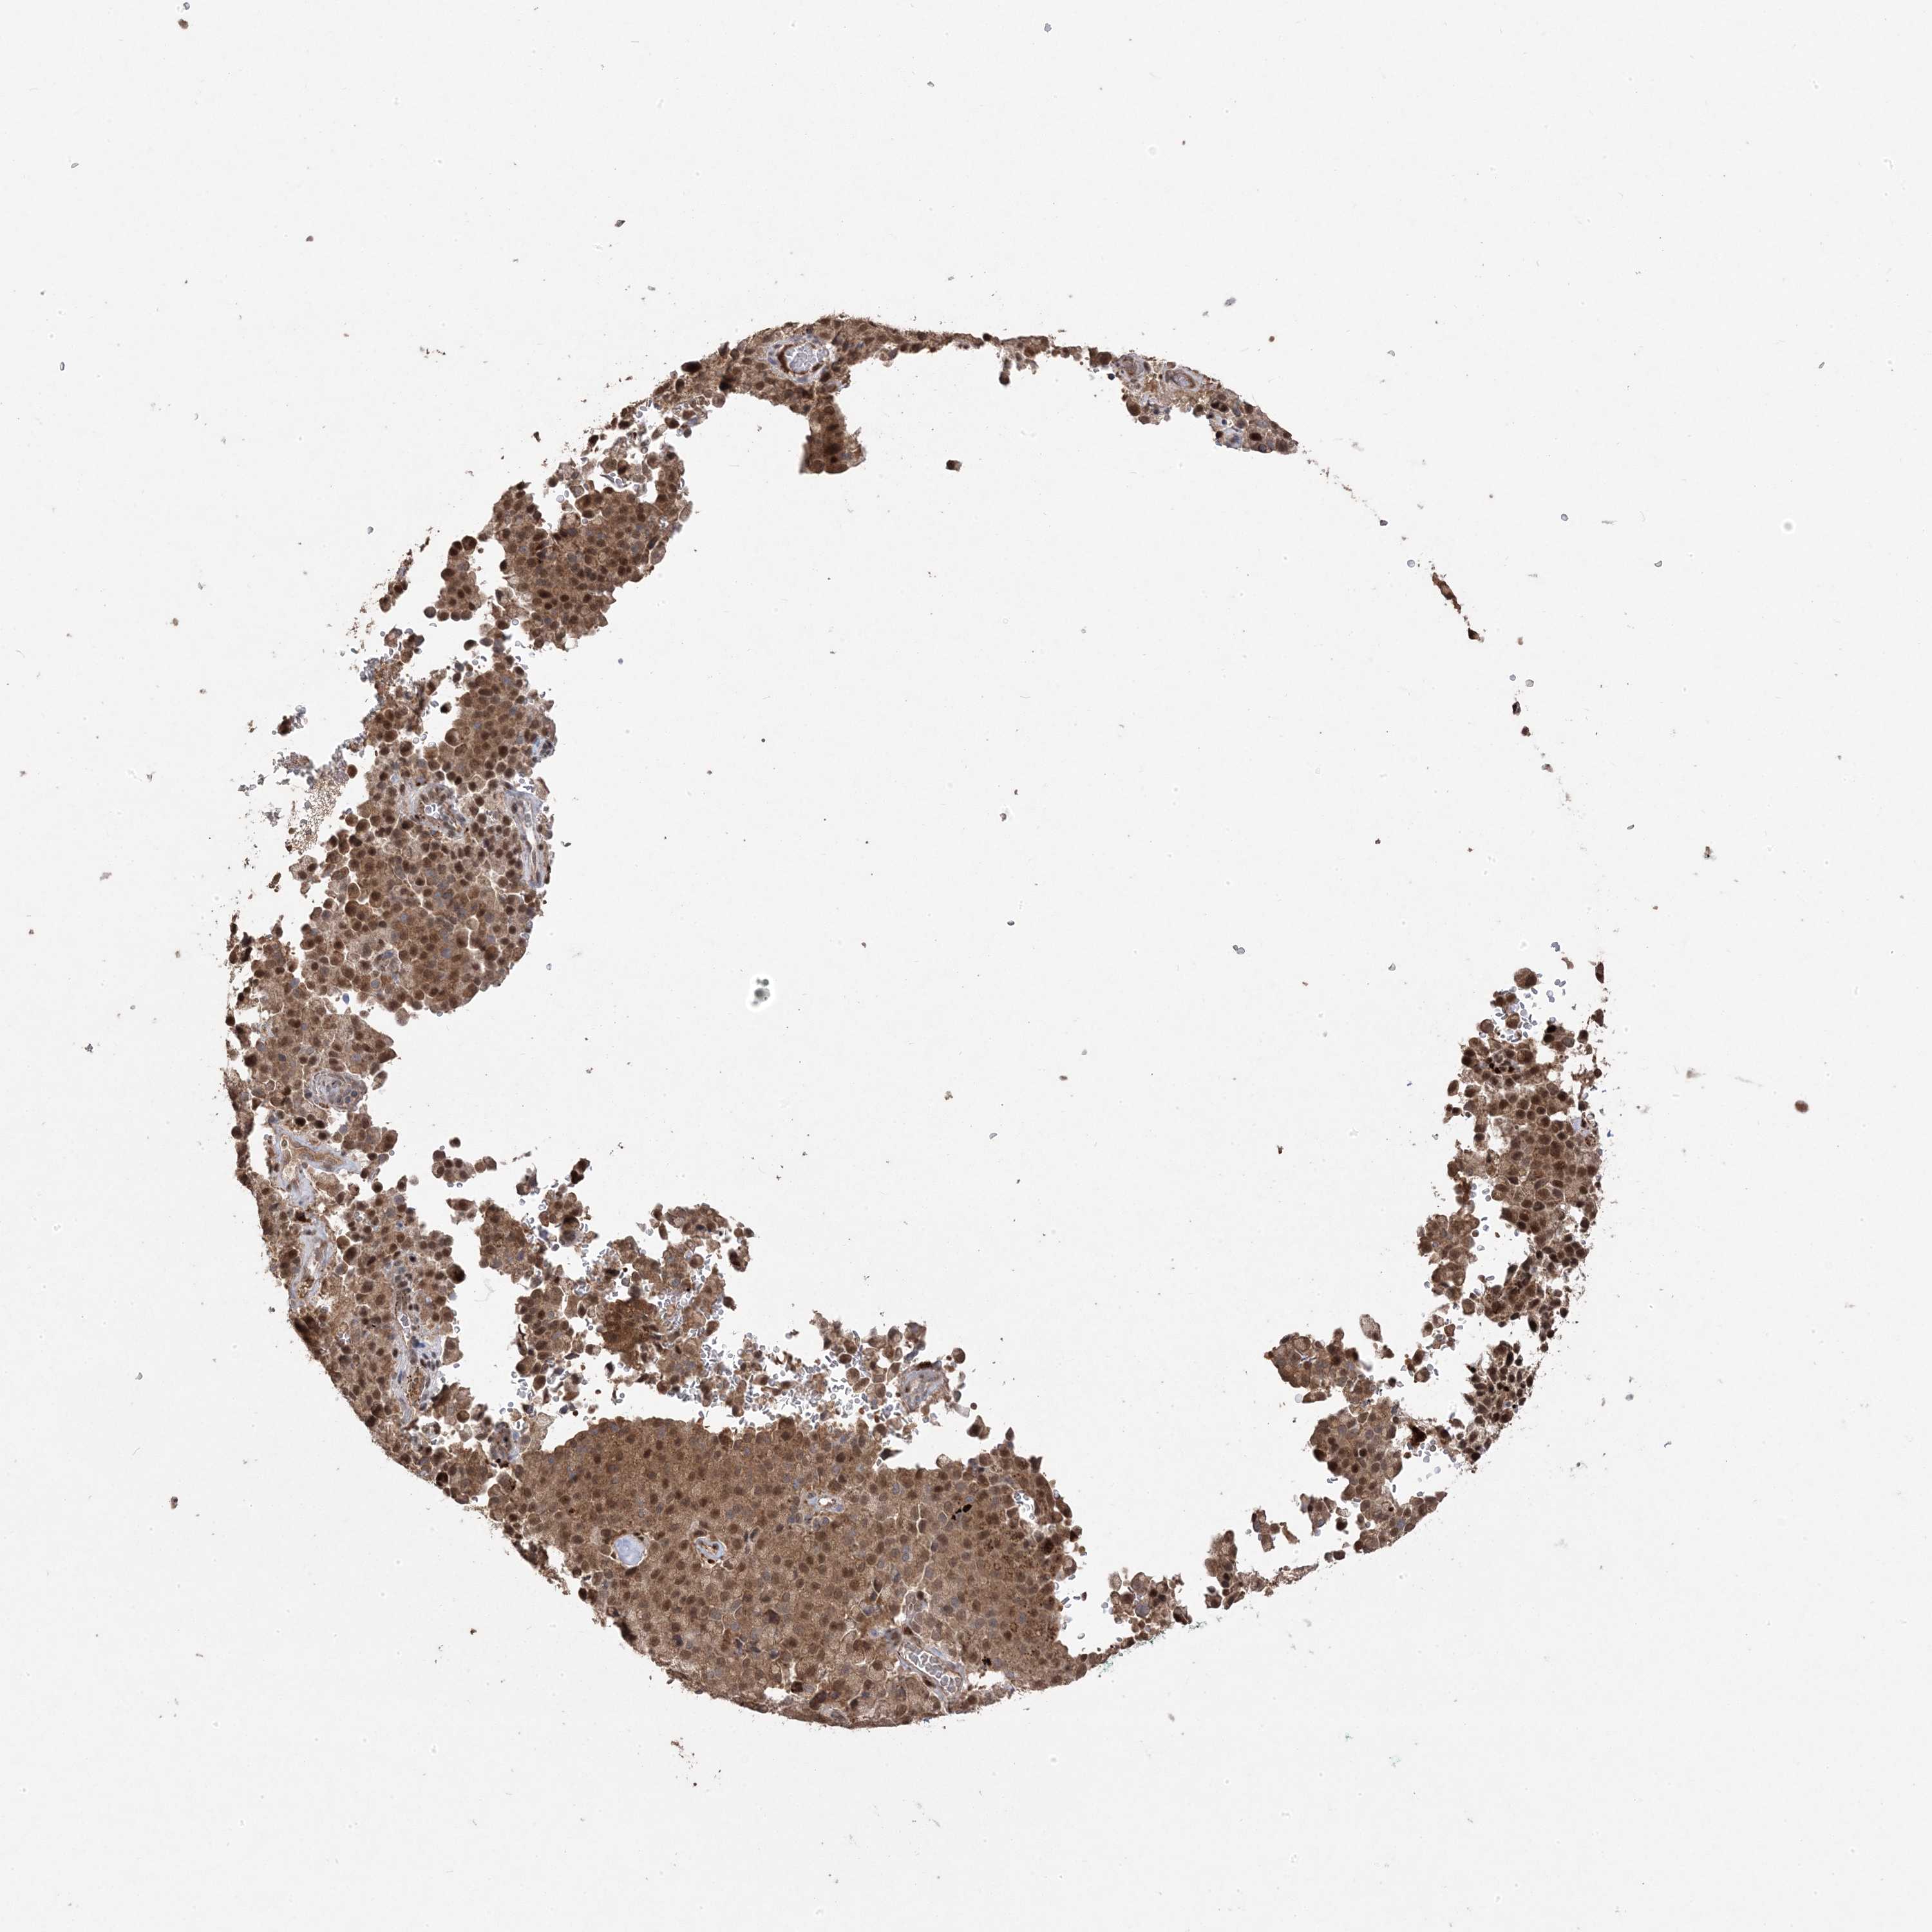

PANCREATIC CANCER - Protein expressioni

A mouse-over function shows sample information and annotation data. Click on an image to view it in a full screen mode. Samples can be filtered based on level of antibody staining by selecting one or several of the following categories: high, medium, low and not detected. The assay and annotation is described here.

Note that samples used for immunohistochemistry by the Human Protein Atlas do not correspond to samples in the TCGA dataset.

Antibody stainingi

Antibody staining in the annotated cell types in the current human tissue is reported as not detected, low, medium, or high, based on conventional immunohistochemistry profiling in selected tissues. This score is based on the combination of the staining intensity and fraction of stained cells.

Each image is clickable and will lead to virtual microscopy that enables deeper exploration of all samples and also displays staining intensity scores, fraction scores and subcellular localization as well as patient and tissue information for each sample.

Antibody HPA030123

Staining

High

Medium

Low

Not detected

Intensity

Strong

Moderate

Weak

Negative

Quantity

>75%

75%-25%

<25%

None

Location

Nuclear

Cytoplasmic/membranous

Cytoplasmic/membranous,nuclear

Adenocarcinoma, NOS